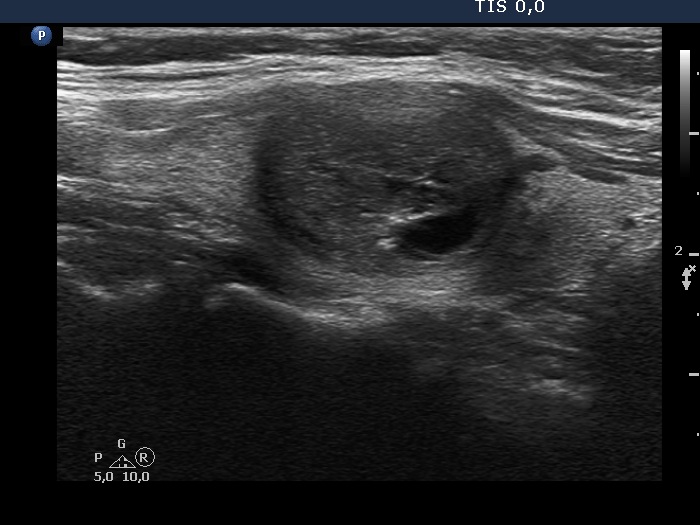

Extrathyroidal spread - case 2128 (ultrasonographic picture 5)

Right lobe, another longitudinal view.